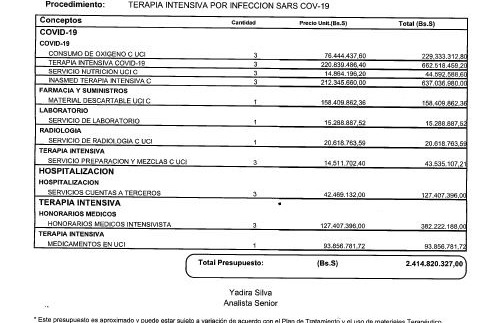

Con los cuidados intensivos, los costos se incrementan considerablemente. A los 3.600 dólares iniciales por la hospitalización se suman otros 10.000 dólares más las medicinas y demás cuidados que necesita (adjuntos los informes y presupuestos).

With intensive care, the costs increase considerably. To the initial $3,600 for the hospitalization is added another $10,000 plus the medicines and other care he needs (reports and estimates attached).

Con los cuidados intensivos, los costos se incrementan considerablemente. A los 3.600 dólares iniciales por la hospitalización se suman otros 10.000 dólares más las medicinas y demás cuidados que necesita (adjuntos los informes y presupuestos).

With intensive care, the costs increase considerably. To the initial $3,600 for the hospitalization is added another $10,000 plus the medicines and other care he needs (reports and estimates attached).